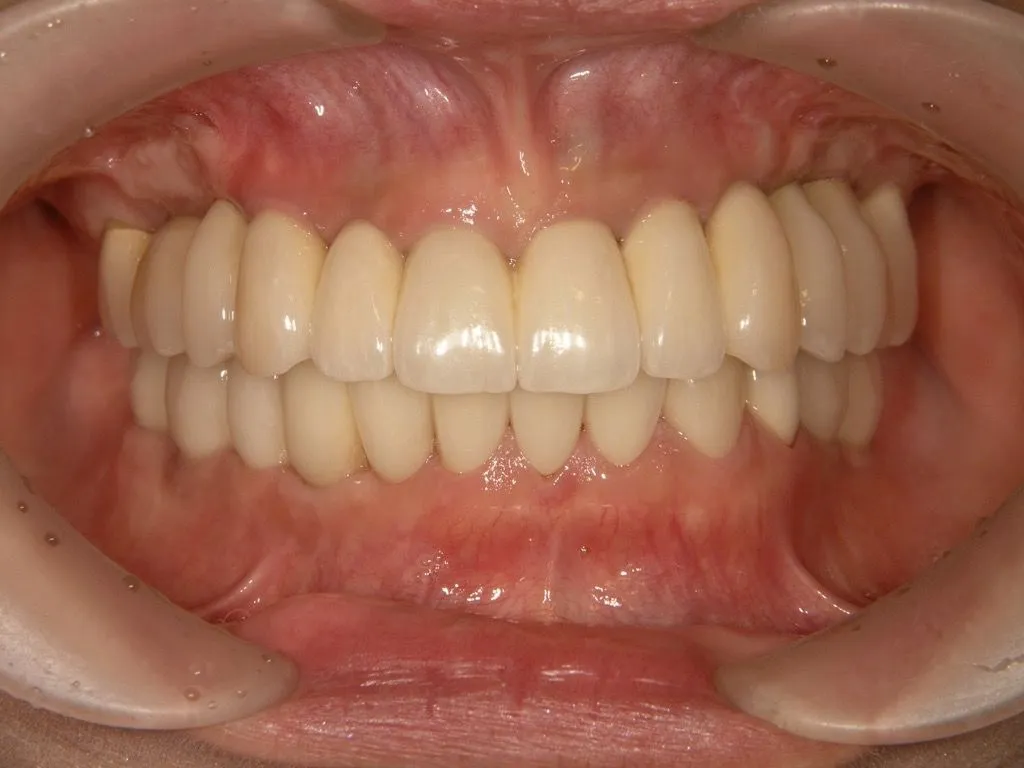

症例

患者様のお悩み | 食事ができない |

|---|---|

治療法・使用素材 | インプラントを用いた全顎的咬合治療 |

患者様の年代 | 40代 |

治療開始年齢 | 49歳 |

治療にかかった期間 | 2年 |

性別 | 女性 |

この治療のリスクについて | |

治療にかかった費用 | 600万 |

治療前

治療後